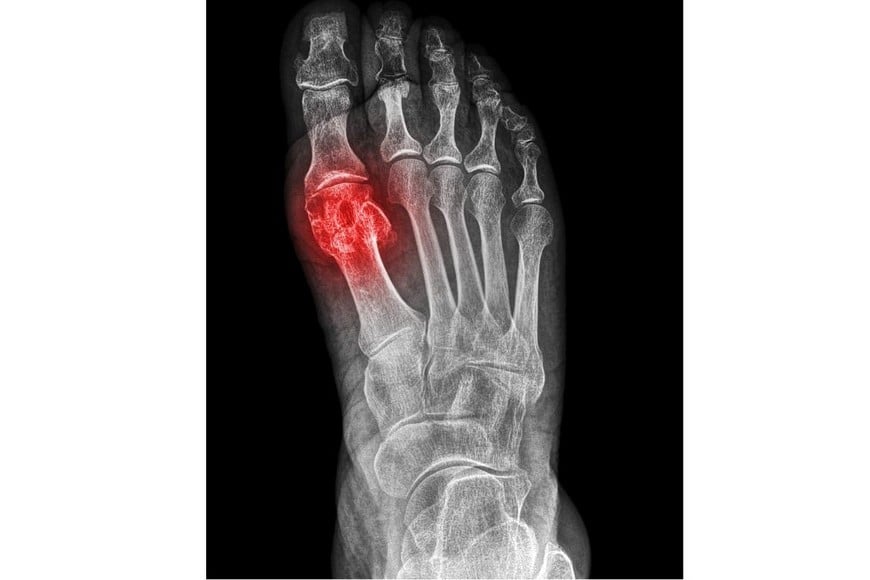

El primer síntoma de una fractura por estrés es un dolor localizado en zonas de carga, como el pie. "En el 80% de los casos se da en los metatarsos, los huesitos de los dedos", agregó el especialista.